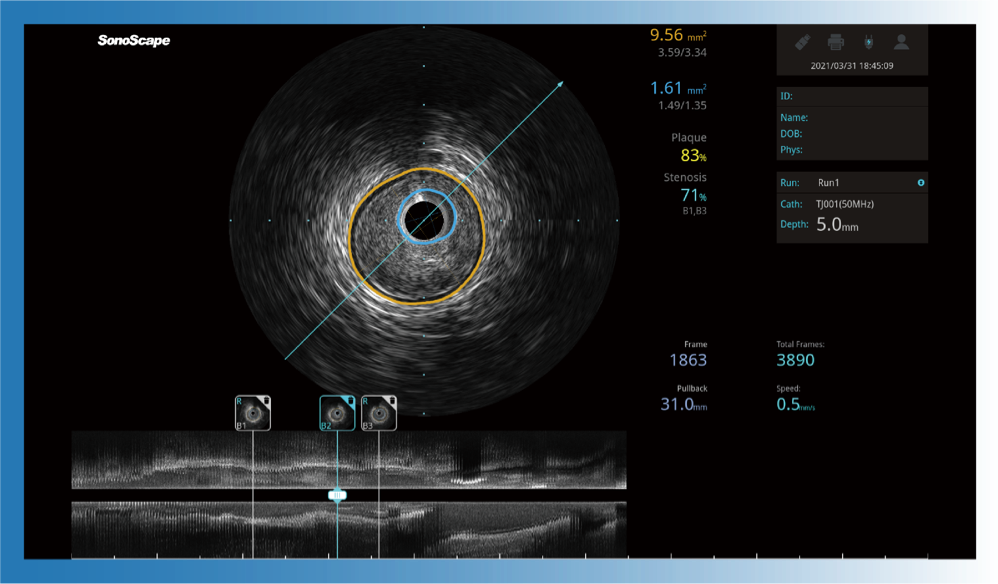

一键智能描迹,自动测量斑块负荷、面积狭窄率等指标,准确率高于90%

临床图